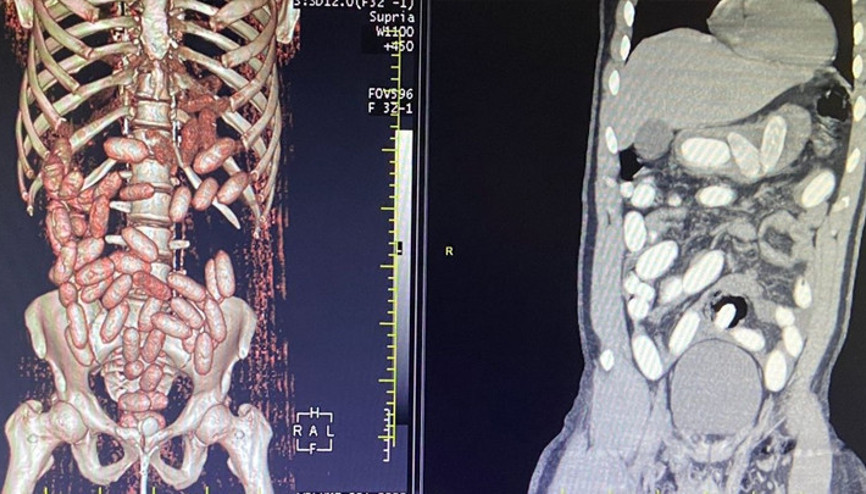

#Ali YerlikayaKONYA’da polisin bir eve düzenlediği operasyonda, İran uyruklu Vahıd Farhang Gangachı'nın (33) ile 4 kişi gözaltına alındı, 1 kilo eroin ele geçirildi. Uyuşturucu kuryeliği yapan ve İran’da iş insanı olduğu belirlenen Gangachı, yuttuğu 300 gram eroini ise hastanede doğal yollarla çıkardı. 5 şüpheli, çıkarıldığı mahkemece tutuklandı.